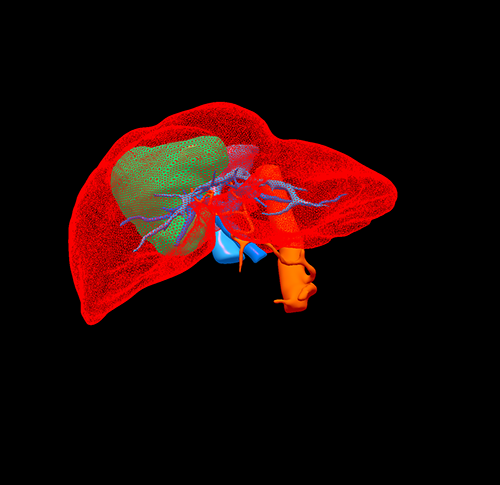

右肝胆管细胞癌-扩大右半肝切除